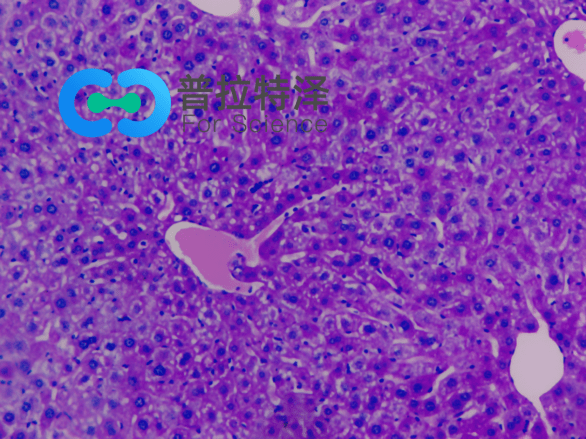

②腎臟疾病診斷

PAS染色在腎臟疾病診斷中同樣發(fā)揮著重要作用。對于腎小球腎炎、腎小管間質(zhì)性腎炎等疾病,PAS染色可以清晰地顯示腎小球基底膜、腎小管及間質(zhì)等結(jié)構的變化,有助于醫(yī)生做出準確的診斷。